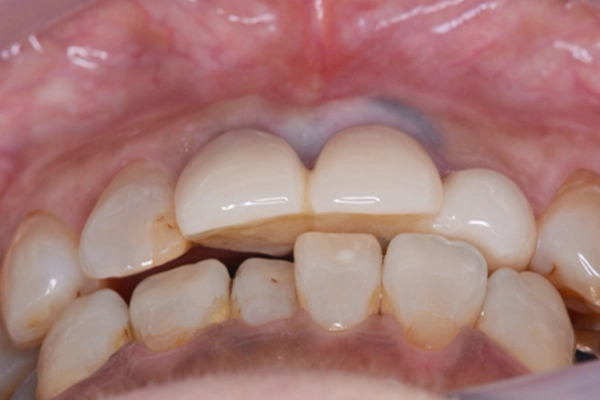

見た目の状態

歯茎のラインと歯の先端のラインが左上2番の影響で不揃いになっていました。